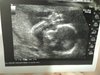

zatem.przedstawiam oto Ida, moje 500gramow szczęścia.